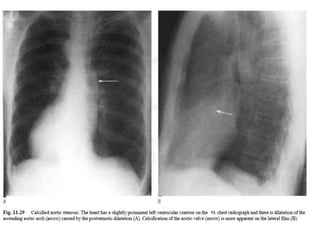

On the lateral film:

• the presence of calcification in the position of

the aortic valve is an important sign, usually

indicating important valve stenosis.

• Some authors suggest this calcification

represents severe aortic stenosis with a

gradient of at least 50 mmHg.

• The chest radiograph : Rounding of the left

ventricular apex indicative of left ventricular

hypertrophy.

• Dilatation of the ascending aortic arch, a result

of the impact of the stenotic jet on the vessel

wall. Variable d/t variation in jet direction

• The degree of dilatation does not correlate with

the severity of stenosis.